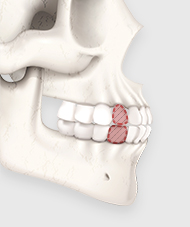

작은 어금니를 발치한 뒤, 위아래 잇몸뼈를 삭제합니다.

제거된 치아와 잇몸뼈만큼 턱뼈를 뒤쪽으로 이동시켜 과도한 돌출 증상을 해소합니다.

돌출입 수술은 단순히 돌출된 입을 밀어 넣는 것이 아니라,

코 끝부터 인중, 입술을 거쳐 턱 끝까지

자연스러운 라인을 완성하는 것이 핵심입니다.

코 끝과 인중, 입술과 턱 끝, 그리고 치아 각도까지 고려하여

입체적인 얼굴 옆 라인을 완성합니다.